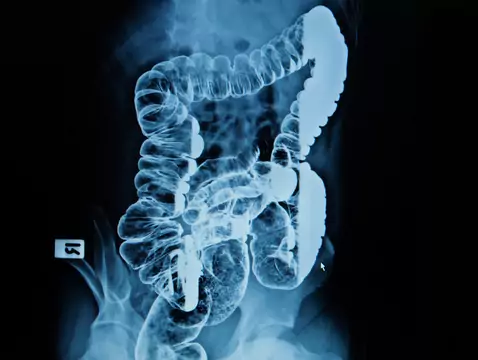

La colonoscopia es un método de diagnóstico inestimable, sin embargo, para que este examen contribuya realmente al proceso de diagnóstico, es necesario cumplir una serie de condiciones. Ante todo, es...